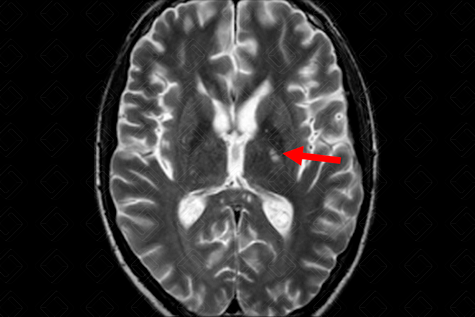

Texto alternativo para a imagem Figura 2. Créditos: Dra. Elazir Mota - Rio de Janeiro/RJ

Descrição da figura 2: Ressonância magnética do crânio T2 evidenciando lesão hiperintensa na cápsula interna esquerda (seta vermelha).

• Os principais achados são: Lesões em "bola de neve" no corpo caloso em T2/Flair, podendo evoluir para lesão perfurante em T1, microinfartos da cápsula interna ("colar de pérolas"), lesões de substância branca e realce meníngeo (figuras 1 e 2).